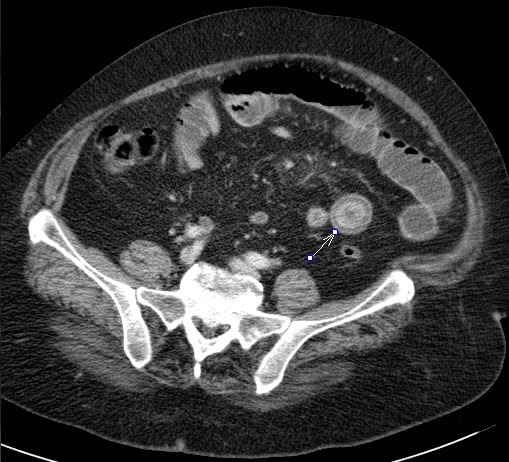

- Appendicitis

- Comb sign

- Crohn disease

- Diverticulitis

- Mesenteric ischemia

- PID

- Sigmoiditis